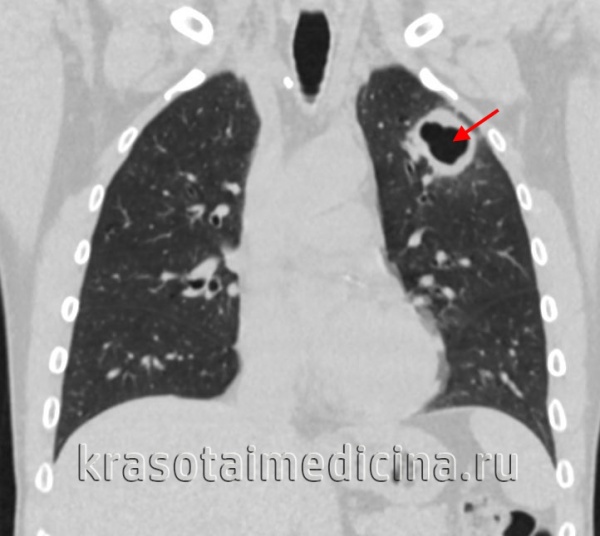

- Лучевая диагностика.Рентгенография легких является обязательным диагностической процедурой, позволяющей выявить характер изменений в легочной ткани (инфильтративный, очаговый, кавернозный, диссеминированный и т. д.), определить локализацию и распространенность патологического процесса. Выявление кальцинированных очагов указывает на ранее перенесенный туберкулезный процесс и требует уточнения данных с помощью КТ или МРТ легких.

Наиболее трудная ситуация в диагностике туберкулеза органов дыхания возникает у больных с клинической симптоматикой в случае отсутствия мокроты, а также тогда, когда в мокроте микобактерии туберкулеза не обнаружены. У таких больных при рентгенологическом исследовании туберкулез может проявляться очаговыми, инфильтративными изменениями в легких, диссеминацией, кавернами, увеличением внутригрудных лимфатических узлов и плевритом. Несмотря на описание рентгенологической картины, характерной для туберкулеза, диагноз этого заболевания не следует ставить только на основании данных клинико-рентгенологического обследования. Перечисленные рентгенологические изменения можно наблюдать не только при туберкулезе, они требуют дифференциальной диагностики. Больным с клинико-рентгенологическими проявлениями, характерными для туберкулеза, при удовлетворительном общем состоянии можно провести бронхоскопию с исследованием аспирата из бронхов или бронхоальвеолярных смывов на микобактерии туберкулеза. Возможно также цитологическое и гистологическое исследование биоптата легочной ткани. Этот метод очень важен и информативен не только для верификации диагноза туберкулеза, но и для дифференциальной диагностики туберкулеза, рака и других заболеваний.